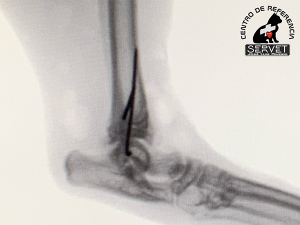

En nuestro caso, varias pequeñas agujas colocadas en el lugar adecuado logran que las fracturas se mantengan estables con abordajes quirúrgicos mínimos.

Preservar la integridad de ligamentos, tendones y músculos es el objetivo de la cirugía de mínima invasión. No nos olvidemos que los tejidos blandos también son necesarios para caminar.